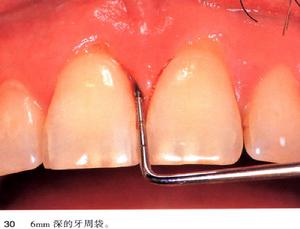

3、逆行性牙髓炎:是牙周病患牙的牙周組織破壞後,感染通過側、副根管或根尖孔進入牙髓引起的牙髓炎症。患牙伴有嚴重的牙周病,同時表現出牙周炎、根尖周炎和牙髓炎的多種特性。有自發性和陣發性疼痛,對冷、熱刺激敏感或有放散痛等急性牙髓炎的表現;也可表現為牙齒鈍痛、脹痛,無明顯自發痛,對冷、熱刺激敏感等慢性牙髓炎的症狀;檢查可見深的牙周袋,或創傷性咬合,牙齒鬆動、叩痛;X線片示根尖周牙槽骨吸收。治療可選用開髓術、根管治療術。

牙周袋鑑別

1.深齲、可復性牙髓炎、慢性牙髓炎(1)疼痛症狀:均可有冷熱痛,但深齲和可復性牙髓炎患牙絕無自發痛病史;慢性牙髓炎可有自發痛史。(2)溫度測驗:用冰棒冷測牙面,深齲患牙的反應與對照牙是相同的,只有當冰水入洞後方引起疼痛;可復性牙髓炎患牙在冷測牙面時即出現一過性敏感。慢性牙髓炎患牙由溫度刺激引起的疼痛反應程度重,持續時間較長久,有時還可出現輕度叩痛。2.急性牙髓炎、三叉神經痛三叉神經痛的發作一般有疼痛“扳機點”,患者每觸及該點即誘發疼痛。患者在訴說病史時,往往忽略此點,應特別加以詳細詢問。再者三叉神經痛較少在夜間發作,冷、熱溫度刺激也不引發疼痛;急性牙髓炎典型的疼痛,可找到痛因患牙。3.急性牙髓炎、齦乳頭炎齦乳頭炎也可出現自發性疼痛,但疼痛性質為持續性脹痛。患牙對溫度測驗的反應同對照牙,也可有一過性敏感的現象。患者對疼痛多可定位。檢查時可發現患者所指示的部位齦乳頭有充血、水腫現象,探診出血,觸痛極為明顯。患處兩鄰牙間可見有食物嵌塞的痕跡或有食物嵌塞史。一般未查及可引起牙髓炎的牙體硬組織損害及其他疾患。